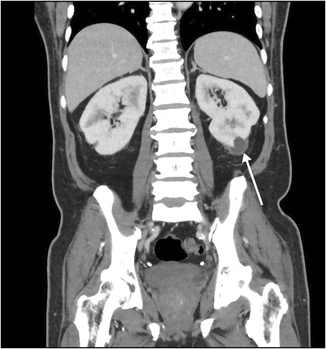

A 65‐year‐old man of Indonesian ethnicity with type 2 diabetes mellitus and hypertension first presented to a peripheral hospital in March 2023 with fevers and diabetic ketoacidosis. He was treated for urosepsis, with Klebsiella pneumoniae isolated in urine and blood cultures. Computed tomography (CT) scan showed multifocal, bilateral thickened perirenal infiltrates, which were discussed at a radiology multidisciplinary meeting and thought to be possibly due to lymphoproliferative disease (Box 1). The infectious diseases team was consulted by the treating medical team; however, as the infectious diseases team was located at the tertiary centre, they could not physically review the patient, and gave advice on antibiotic therapy and duration over the phone. The patient was treated with three days of intravenous (IV) antibiotics and discharged on oral amoxicillin with clavulanic acid, completing a 14‐day antibiotic course. Outpatient screening tests for lymphoproliferative disease and haematology follow‐up were scheduled, with a repeat CT scan planned for three months post‐discharge. Notably, a month prior to his hospital presentation, he travelled to Indonesia, where he required overnight hospital admission for haematemesis.

Box 1 – Computed tomography scan (coronal plane) showing thickened perirenal infiltrates around the kidney (arrow)